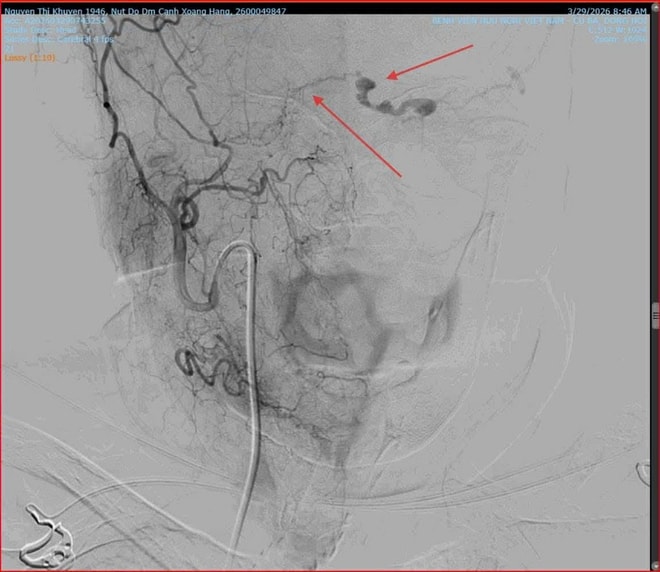

Khi thăm khám cho bệnh nhân, các bác sĩ Khoa Mắt phát hiện mắt trái của cụ K. giảm thị lực, tăng nhãn áp, lồi mắt, giãn tĩnh mạch thượng củng mạc, phù nề kết mạc, hạn chế vận nhãn. Nghi ngờ bệnh nhân bị rò động mạch cảnh xoang hang trái, các bác sĩ đã chỉ định chụp X- Quang số hoá xoá nền (DSA) và có kết quả rò động mạch cảnh xoang hang bên trái.

Vị trí rò động mạch (ảnh trái) và sau khi can thiệp bít lỗ rò (ảnh phải).